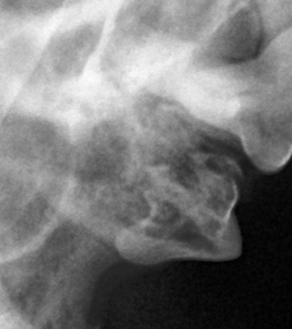

덴탈 X-ray를 통해 치아 내부 상태를 정확히 파악한 후, 아이에게 불필요한 고통 없이 최선의 결정을 내릴 수 있도록 안내합니다.